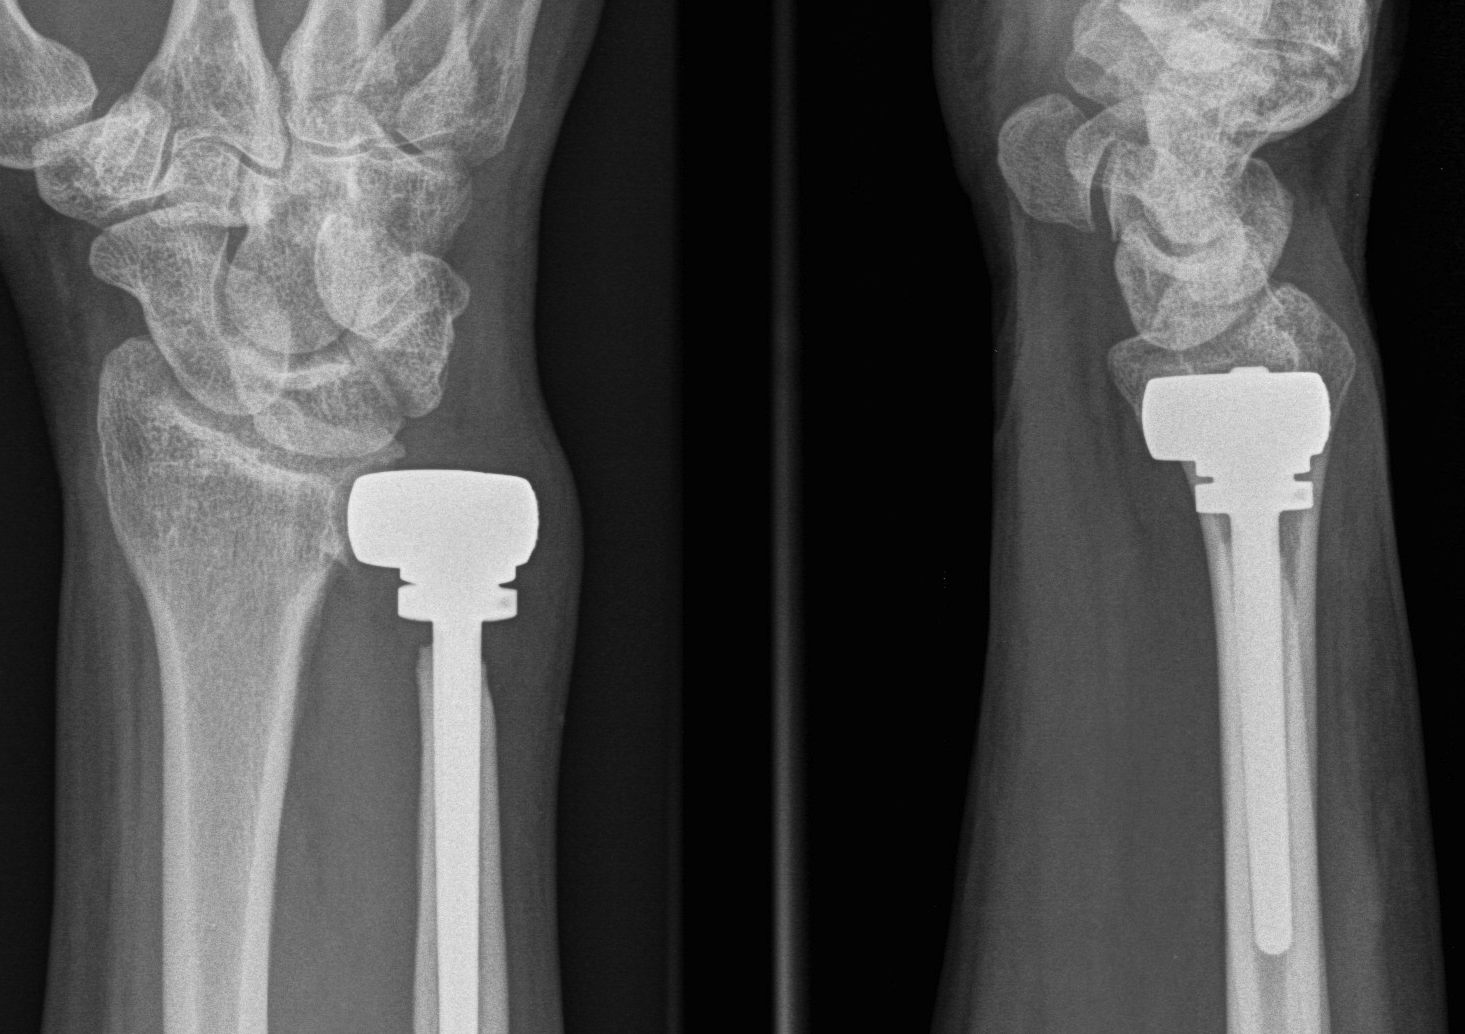

DRUJ Replacement

Options

Hemiarthroplasty

Total joint arthroplasty

DRUJ hemiarthroplasty

Technique total joint arthroplasty

Aptis DRUJ total joint arthroplasty

Dorsal approach

- between 5th and 6th extensor compartment

- open extensor retinaculum

- resect proximal ulna

- prepare radius and apply radial plate checking implant position with fluoroscopy

- intramedullary ream ulna

- press fit ulna prosthesis

Results

Stougie et al J Wrist Surg 2023

- 53 Aptis DRUJ total arthoplasty with 4 year follow up

- implant survival 92%

- revision surgery 41%

- complication rate 64%

- patient satisfaction 72%

- 32 DRUJ hemiarthroplasty followed for 3 years

- metallic implants: reoperation 10%, failure 30%

- pyrocarbon implants: reoperation 14%, failure 18%